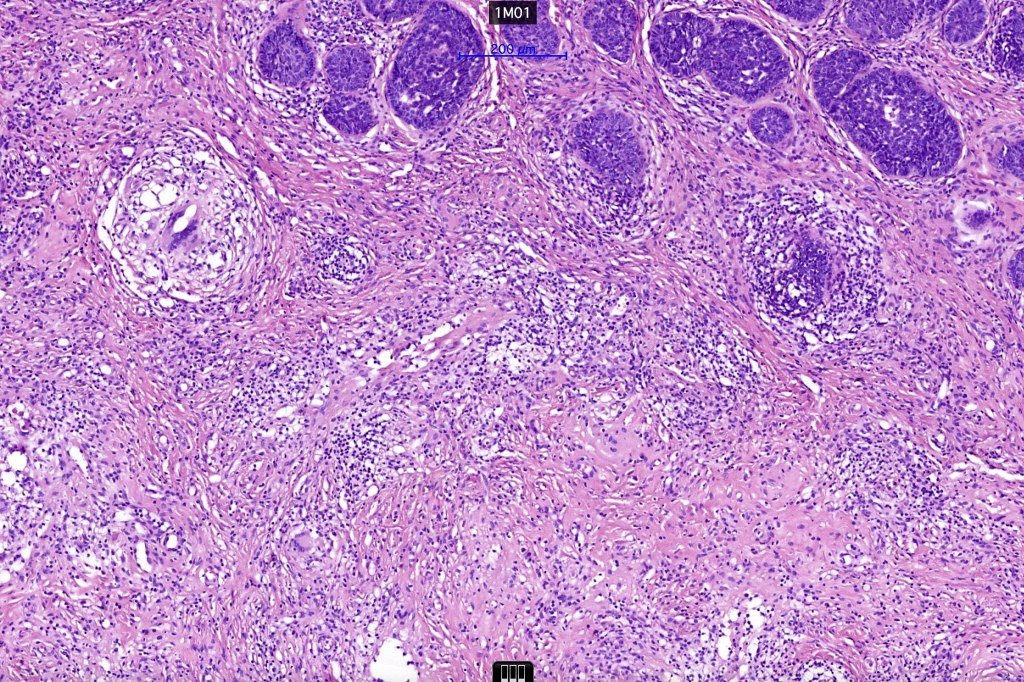

•The classical appearance consists of keratocysts & lobules of basaloid cells

•Some tumors are devoid of keratocysts

•Perifollicular mesenchyme is always conspicuous and sometimes densely aggregated are seen indenting the baslaloid lobules (papillary mesenchymal bodies)

Trichoepithelioma should be distinguished from trichoblastoma since the latter is very rarely syndromic. Trichoepithelioma is largely a dermal tumor whereas trichoblastoma often extends from the dermis into subcutaneous fat or deeper in very large examples. Papillary mesenchymal bodies are much better formed and generally more obvious in trichoepithelioma. Trichoepithelioma must also be distinguished from basal cell carcinoma. Retraction artifact & stromal mucin are features of basal cell carcinoma and not trichoepithelioma. Papillary mesenchymal bodies are not seen in basal cell carcinoma.